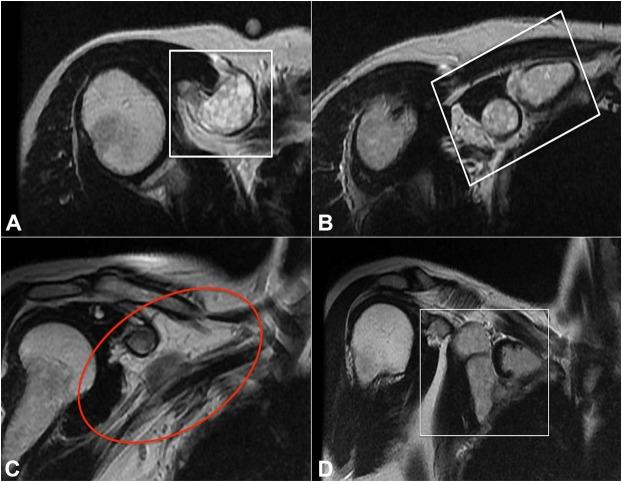

Hydatidosis is a frequent infestation in large endemic areas, caused by helminths. Primary localization within the muscle or bone tissues is rare. We report the case of a 52-year-old woman with a cystic lesion located in the right pectoralis minor muscle, who was initially diagnosed with cystic lymphangioma by imaging examination. She was submitted for surgical treatment; in block resection of the tumor along with the involved muscle was performed. The histopathological diagnosis was of hydatid cyst. The contribution of the ancillary lab tests is analyzed for a precise preoperative diagnostic approach. This case well illustrates that the most likely is not always what it appears to be. Facing of a cystic lesion in the lungs, liver or muscle, clinicians should always think on hydatid disease, particularly in endemic areas.

包虫病在大片流行地区是一种常见的寄生虫感染病。在肌肉或骨组织中的原发性定位很少见。我们报告一例52岁女性,其右胸小肌有一个囊性病变,最初经影像学检查诊断为囊性淋巴管瘤。她接受了手术治疗,术中对肿瘤连同受累肌肉进行了整块切除。组织病理学诊断为包虫囊肿。分析了辅助实验室检查对精确术前诊断方法的作用。该病例很好地说明了最有可能的情况并不总是表面看上去的那样。面对肺、肝或肌肉中的囊性病变,临床医生应始终考虑到包虫病,尤其是在流行地区。